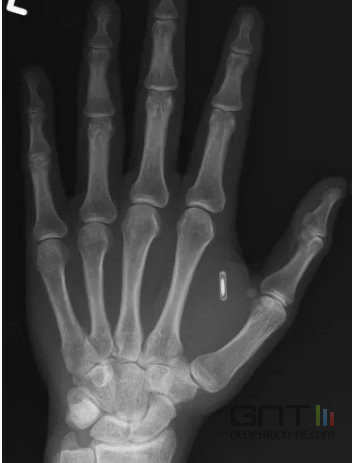

Zi Teng Wang RFID

RFID